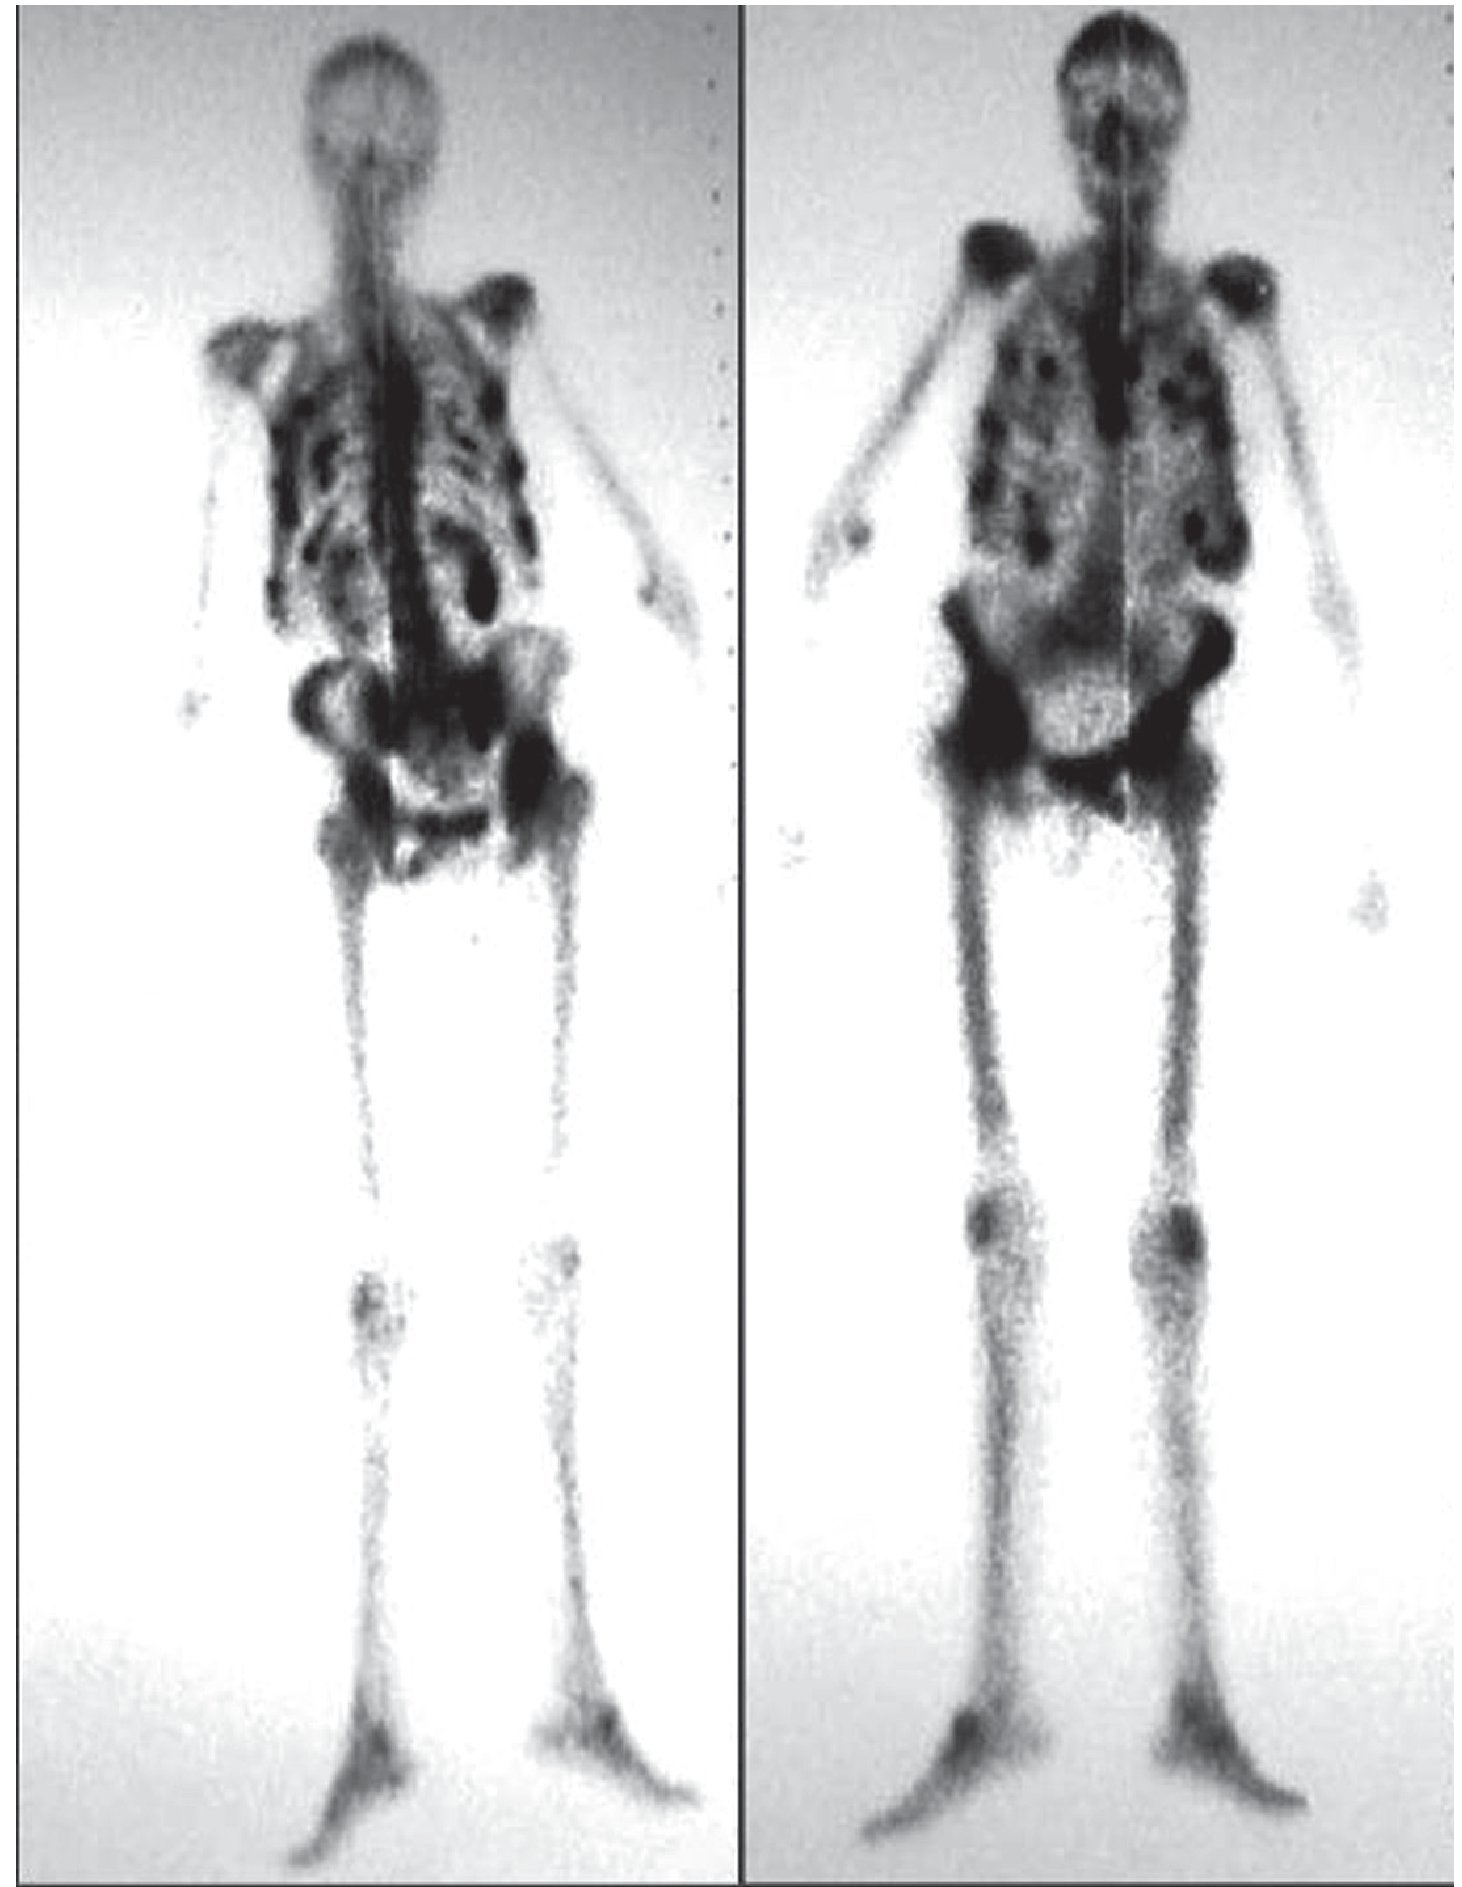

Además, podemos encontrar hipercaptaciones focales a diversos niveles, tanto óseas como extraóseas, que variarán en función de la patología concreta del paciente (figs. 1 y 2).

Fig. 2. Gammagrafía ósea con MDP-99mTc sobre miembros inferiores donde se aprecia calcificación extraósea sobre muslo izquierdo, hallazgo frecuente en las enfermedades metabólicas óseas.